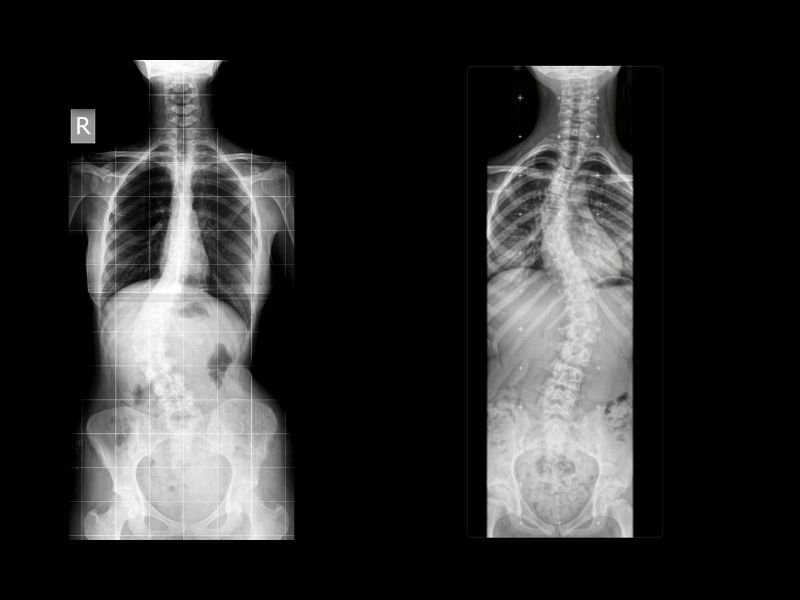

A escoliose idiopática é uma curvatura anormal da coluna vertebral, geralmente diagnosticada na adolescência sem causa aparente. A evolução da curva pode variar: em alguns casos ela permanece estável, mas em outros a curvatura pode piorar, trazendo dor, alterações posturais e, nos casos mais graves, comprometimento da função pulmonar.

O diagnóstico da escoliose é feito por meio de exame físico e radiografias. O médico especialista em coluna pode solicitar exames adicionais para avaliar o risco de progressão da escoliose e indicar se o uso de colete ortopédico ou até cirurgia de escoliose é recomendada.